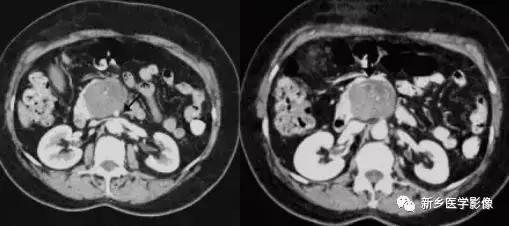

2.影像学诊断:胰腺淋巴瘤在影像学上两种表现形式 :(1)病变弥漫侵润, 表现为胰腺增大;(2)胰腺内边界清晰的限局性的肿块。肿瘤一般均质, 密度低, T 1WI 上信号低于正常胰腺, T 2WI 上信号略高于正常胰腺, 增强扫描示病变乏血供。病变区罕有坏死、出血或钙化。在腹膜后及腹腔内可有肿大淋巴结。部分患者可有胆管扩张。